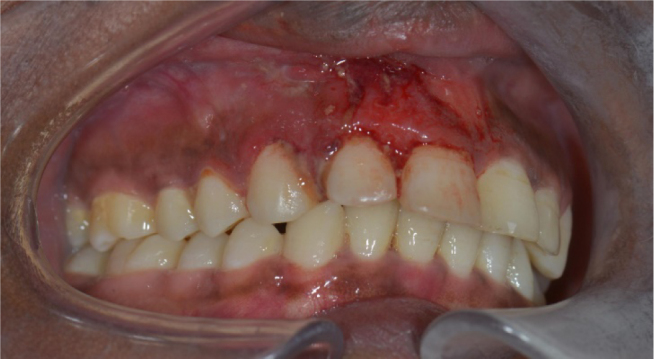

Rhabdomyosarcoma is the most common soft tissue sarcoma in children but is less frequent in adults, with the head and neck region as primary site. Magnetic resonance imaging (MRI) is the preferred diagnostic imaging tool, though its imaging characteristics are relatively non‑specific and overlap with other soft tissue sarcomas. The prognosis of rhabdomyosarcoma depends on the primary tumour site and size, with parameningeal head and neck localisations having a less favourable prognosis due to the higher risk of spread. Therefore, further imaging including brain and spinal MRI is recommended. Teaching point: The prognosis of rhabdomyosarcoma depends on the primary tumour site and size, with parameningeal head and neck localisations having a less favourable prognosis due to the higher risk of spread.

Abstract Image